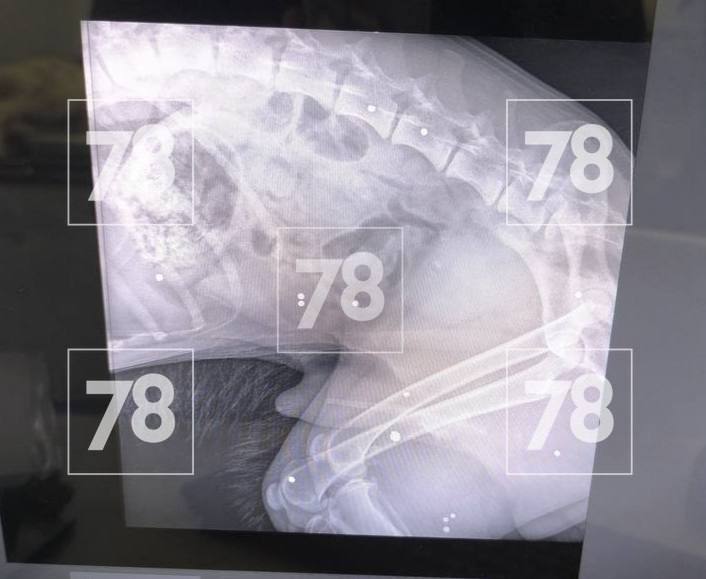

Рентген показал, что в животное выстрелили дробью. Врачи провели операцию, но вытащить смогли только три снаряда.